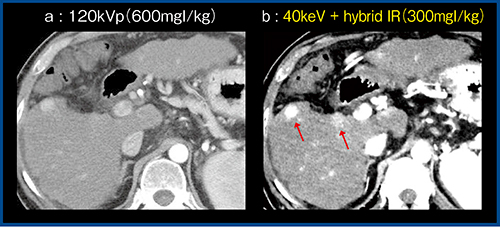

低keV画像(低エネルギー画像)ではコントラストが向上し,低管電圧撮影と同様の効果が期待できる(図1)。また,合理的な造影剤量の低減も可能である。図2は肝細胞がんの経過観察の症例であるが,120kVpの造影CT画像(a)と比較して,造影剤量を半減(300mgl/kg)して取得した40keV画像にノイズ低減目的にhybrid IRを併用した画像(b)では,コントラストが向上して描出能が改善し,病変が視認しやすくなっている(↑)。

図2 40keV+hybrid IRによる造影剤量の低減